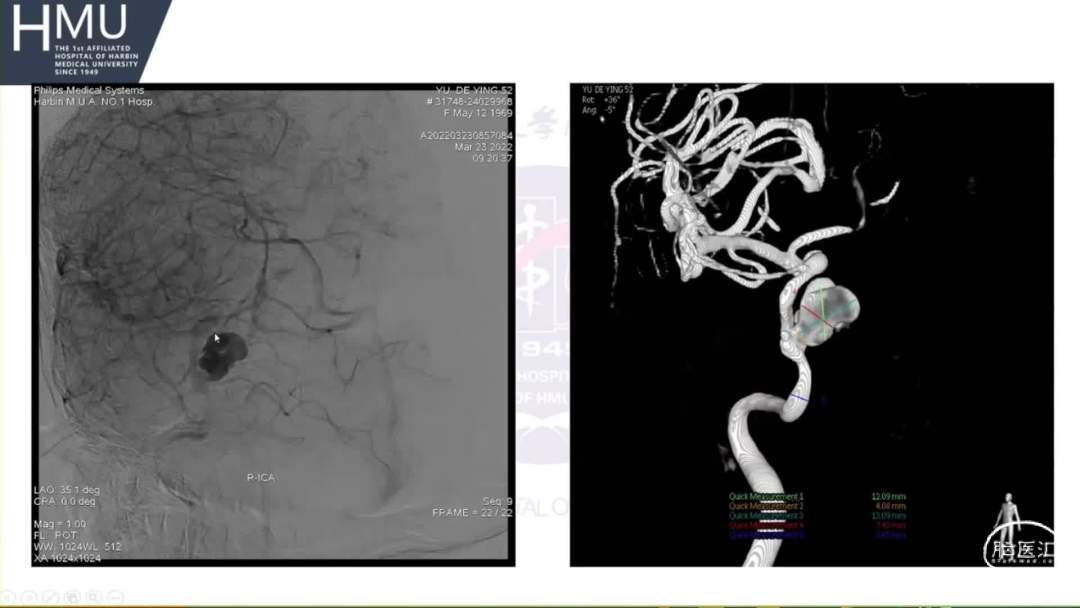

●女,52岁,因“头痛4日,右侧眼脸下垂1日” 入院

入院前4日无诱因出现后枕部头痛,呈针刺样持续性疼痛,入院前1日,出现右眼睑下垂伴眼球胀痛

神清语明,右眼球固定,双侧瞳孔

左:右=2.5mm:5mm,右眼光反射消失,颈强阳性。